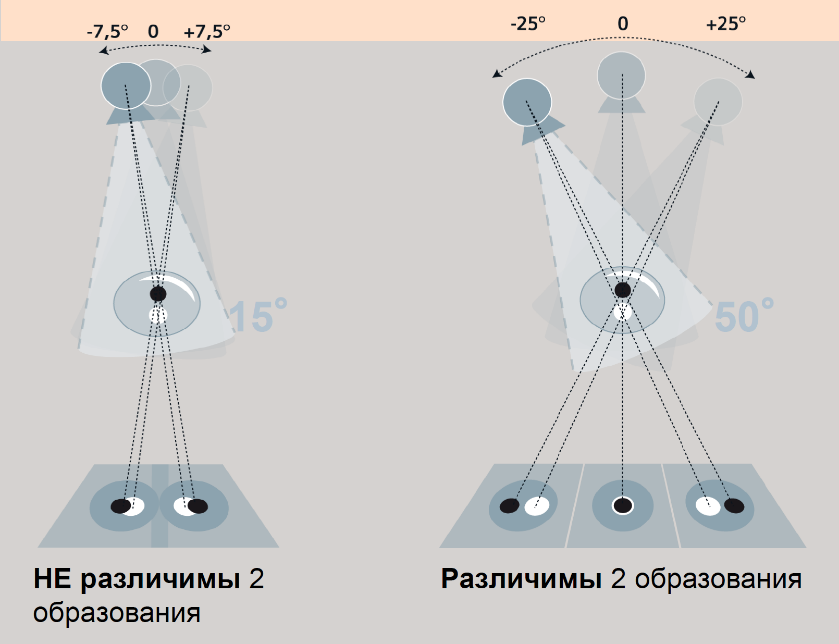

Факторы качества цифрового томосинтеза (DBT)

- Угол наклона рентгеновского излучателя. Больший угол даёт больше информации, т.к. уменьшается степень наслоения соседних объектов.

- Количество получаемых проекций. Чем больше количество проекций, тем меньше уровень артефактов.